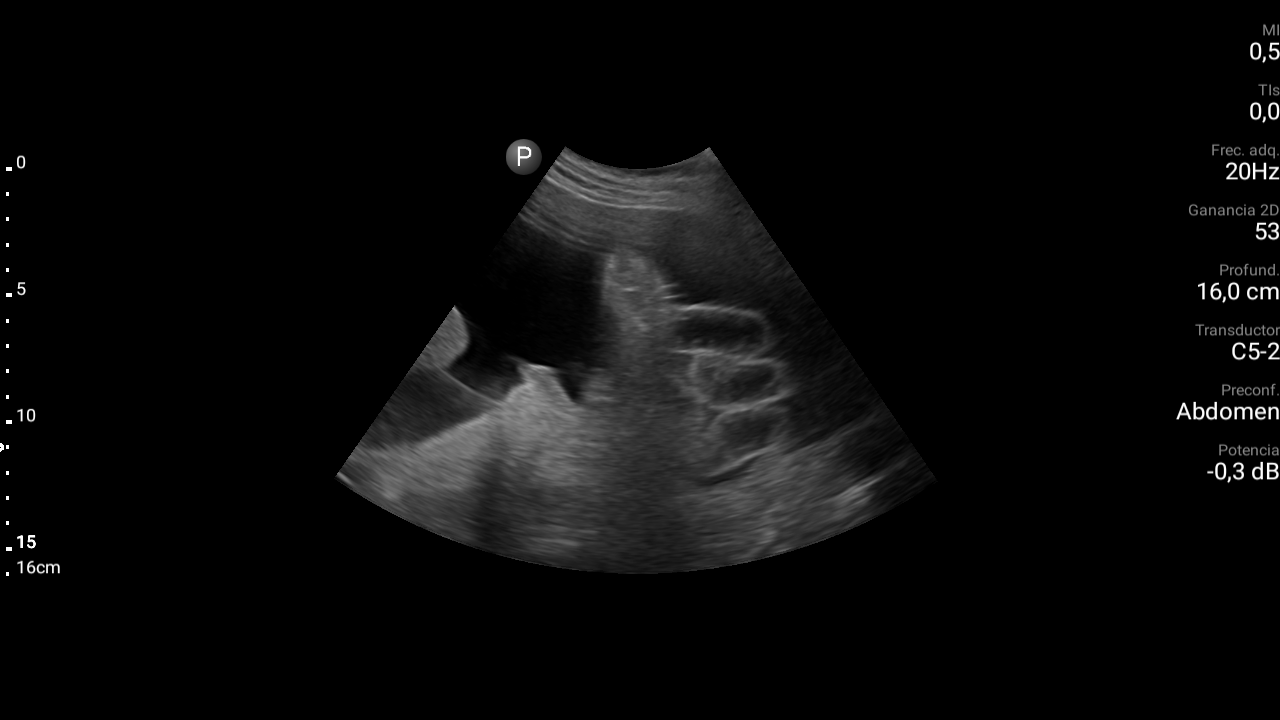

Presencia de ascitis perihepática, periesplénica. En la pelvis se visualizan asas intestinales con aspecto congestivo.

Hígado parcialmente visualizado esteatósico sin lesiones focales.

Derrame pleural bilateral moderado.